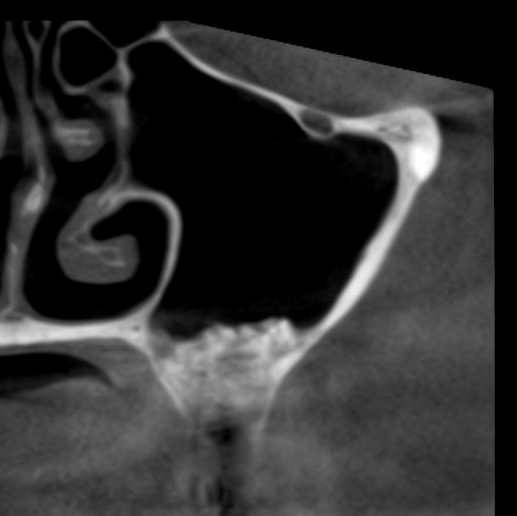

Для этого мы сделали КЛКТ:

И КЛКТ показала нам, что с имплантатами и окружающей костью всё зашибись. Через 12 лет после операции, отсутствия наблюдения, пофигизма в замене временных коронок! Нужны ли тебе еще какие-нибудь доводы в пользу долгосрочной эффективности метода?

Признаюсь, не совсем понимаю необходимости назначения консультации ЛОР-врача всем пациентам поголовно. Скажем, если у пациента нет жалоб со стороны носовой полости, нет вазомоторного или аллергического ринита, на КЛКТ все носовые пазухи воздушные и чистые, их сообщение с носовой полостью не нарушено — каков смысл гонять пациента к ринологу?